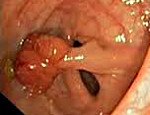

Анальный полип

Анальный полип является предраковым опухолевым образованием слизистой прямой кишки. Долгое время протекает бессимптомно; проявлениями заболевания служат кровяные и/или слизистые выделения, иногда значительные кровотечения; запоры или поносы; ложные позывы; ощущения инородного тела или неполного опорожнения кишечника. Диагноз ставится на основании пальцевого исследования, аноскопии, ректоромано- или колоноскопии, рентгенологического исследования с контрастированием, биопсии. Лечение включает в себя малоинвазивные хирургические методики: электрокоагуляцию и радиоволновую терапию.

Анальный полип представляет собой доброкачественное новообразование, исходящее из слизистой аноректальной области. Полипозные выросты могут быть единичными и множественными, располагаться обособленно и группами; быть связанными со слизистой посредством ножки или широким основанием. Форма опухоли грибовидная, ветвящаяся, шаровидная или овальная. Размер варьирует от просяного зерна до лесного ореха (2-3 см в диаметре). Встречается во всех возрастных категориях, начиная с детского возраста. Полипы бывают железистого происхождения (встречаются чаще всего), гиперпластического или ворсинчатого. Патологический процесс, как правило, протекает бессимптомно до момента значительного увеличения опухоли или выпадения полипа наружу за счет длинной ножки.

По морфологической принадлежности в прокологии выделяют аденоматозные, ворсинчатые, фиброзные и смешанные полипы. Наиболее часто встречаются опухоли в виде аденомы; они не отличаются по виду от слизистой оболочки (имеют нежно-розовый цвет и нормальный сосудистый рисунок), представляют собой плотные новообразования, гладкие на ощупь. Ворсинчатые полипы крепятся широким основанием, имеют губчатую структуру и легко кровоточат. Фиброзные опухоли чаще всего имеют ножку и довольно часто могут произрастать из геморроидального узла. Из-за разрастания соединительнотканной ножки полипы могут выпадать из прямой кишки наружу.